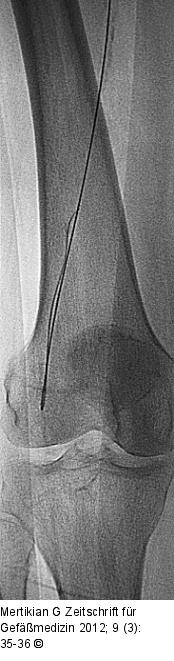

Abbildung 2: Re-entry-Katheter

Subintimale Passage des 0,035''-Terumo-Drahtes |